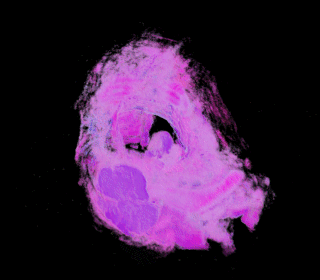

3D Models in VRML from Serial Section Images by Automated Image Registration and Advanced Alpha Mapping. (Illustrated by serial sections of a bronchial carcinoid tumour)

(Click Here)